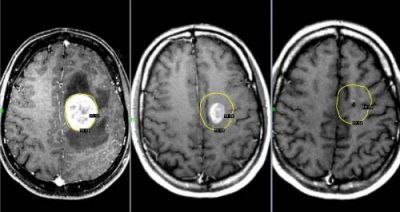

Опухоли мозга

Это новообразования, локализующиеся в тканях мозга. Они могут быть доброкачественными или злокачественными. Доброкачественные опухоли не метастазируют, имеют четкие границы роста и могут лечиться без операции, не вызывая рецидивов.

Злокачественные опухоли быстро прорастают в соседние ткани и могут образовывать метастазы в нескольких участках мозга.

Такие опухоли плохо поддаются лечению, и на поздних стадиях их развития спасти пациента практически невозможно.

*Клиническая картина*

Болевые ощущения постоянные и со временем усиливаются. При движении боль становится сильнее. Сначала она локализуется в области опухоли, затем, с увеличением внутричерепного давления, распространяется на лобную и затылочную части. Наибольший дискомфорт наблюдается ночью и утром из-за скопления жидкости. Вены не справляются с оттоком крови, что приводит к отечности и застойным явлениям. Боли могут быть давящими, распирающими или пульсирующими.

К головным болям может добавляться рвота. При физической нагрузке или кашле боль усиливается, может возникать двоение в глазах и временная потеря зрения. У пациента кружится голова, нарушается координация движений, могут неметь конечности и ослабевать мышцы.

Иногда наблюдаются эпилептические припадки и спутанность сознания.

*Вмешательство врача*

Необходима помощь терапевта, нейрохирурга, онколога и радиолога-онколога.

*Диагностирование*

Для диагностики используются МРТ, ПЭТ, КТ, ангиография и другие методы.

*Лечение*

* Для облегчения боли на ранних стадиях заболевания врачи рекомендуют мочегонные препараты и кортикостероиды, которые помогают снять отек и нормализовать кровоснабжение пораженного участка.

* Удаление опухоли с помощью лазера, эндоскопии и ультразвука.

* Иссечение опухоли, что является травматичным методом. Способы иссечения включают трепанацию черепа или удаление костных фрагментов.